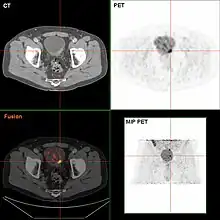

If invasive or high grade (includes carcinoma in situ) cancer is detected on TURBT, an MRI and/or CT scan of the abdomen and pelvis or urogram and CT chest should be conducted for disease staging and to look for cancer spread (metastasis).[56] Increase in alkaline phosphatase levels without evidence of liver disease should be evaluated for bone metastasis by a bone scan.[57] Although 18F-fluorodeoxyglucose (FDG)-positron emission tomography (PET)/CT has been explored as a viable method for staging, there is no consensus to support its role in routine clinical evaluations.[54]

The most common sites for bladder cancer metastases are the lymph nodes, bones, lung, liver, and peritoneum.[78] The most common sentinel lymph nodes draining bladder cancer are obturator and internal iliac lymph nodes. The location of lymphatic spread depends on the location of the tumors. Tumors on the superolateral bladder wall spread to external iliac lymph nodes. Tumors on the neck, anterior wall and fundus spread commonly to the internal iliac lymph nodes.[79] From the regional lymph nodes (i.e. obturator, internal and external lymph nodes) the cancer spreads to distant sites like the common iliac lymph nodes and paraaortic lymph nodes.[80] Skipped lymph node lesions are not seen in bladder cancer.[79]